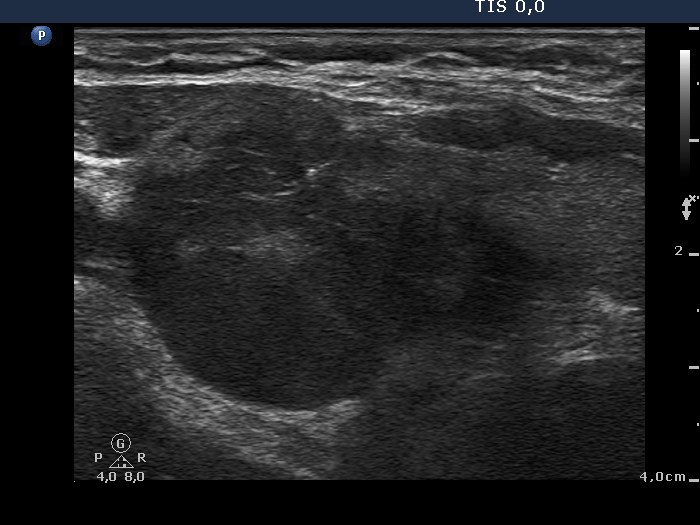

Ultrasonography. There was a large and several smaller, irregular, hypoechogenic lesions in the right lobe. The vascularization was decreased.